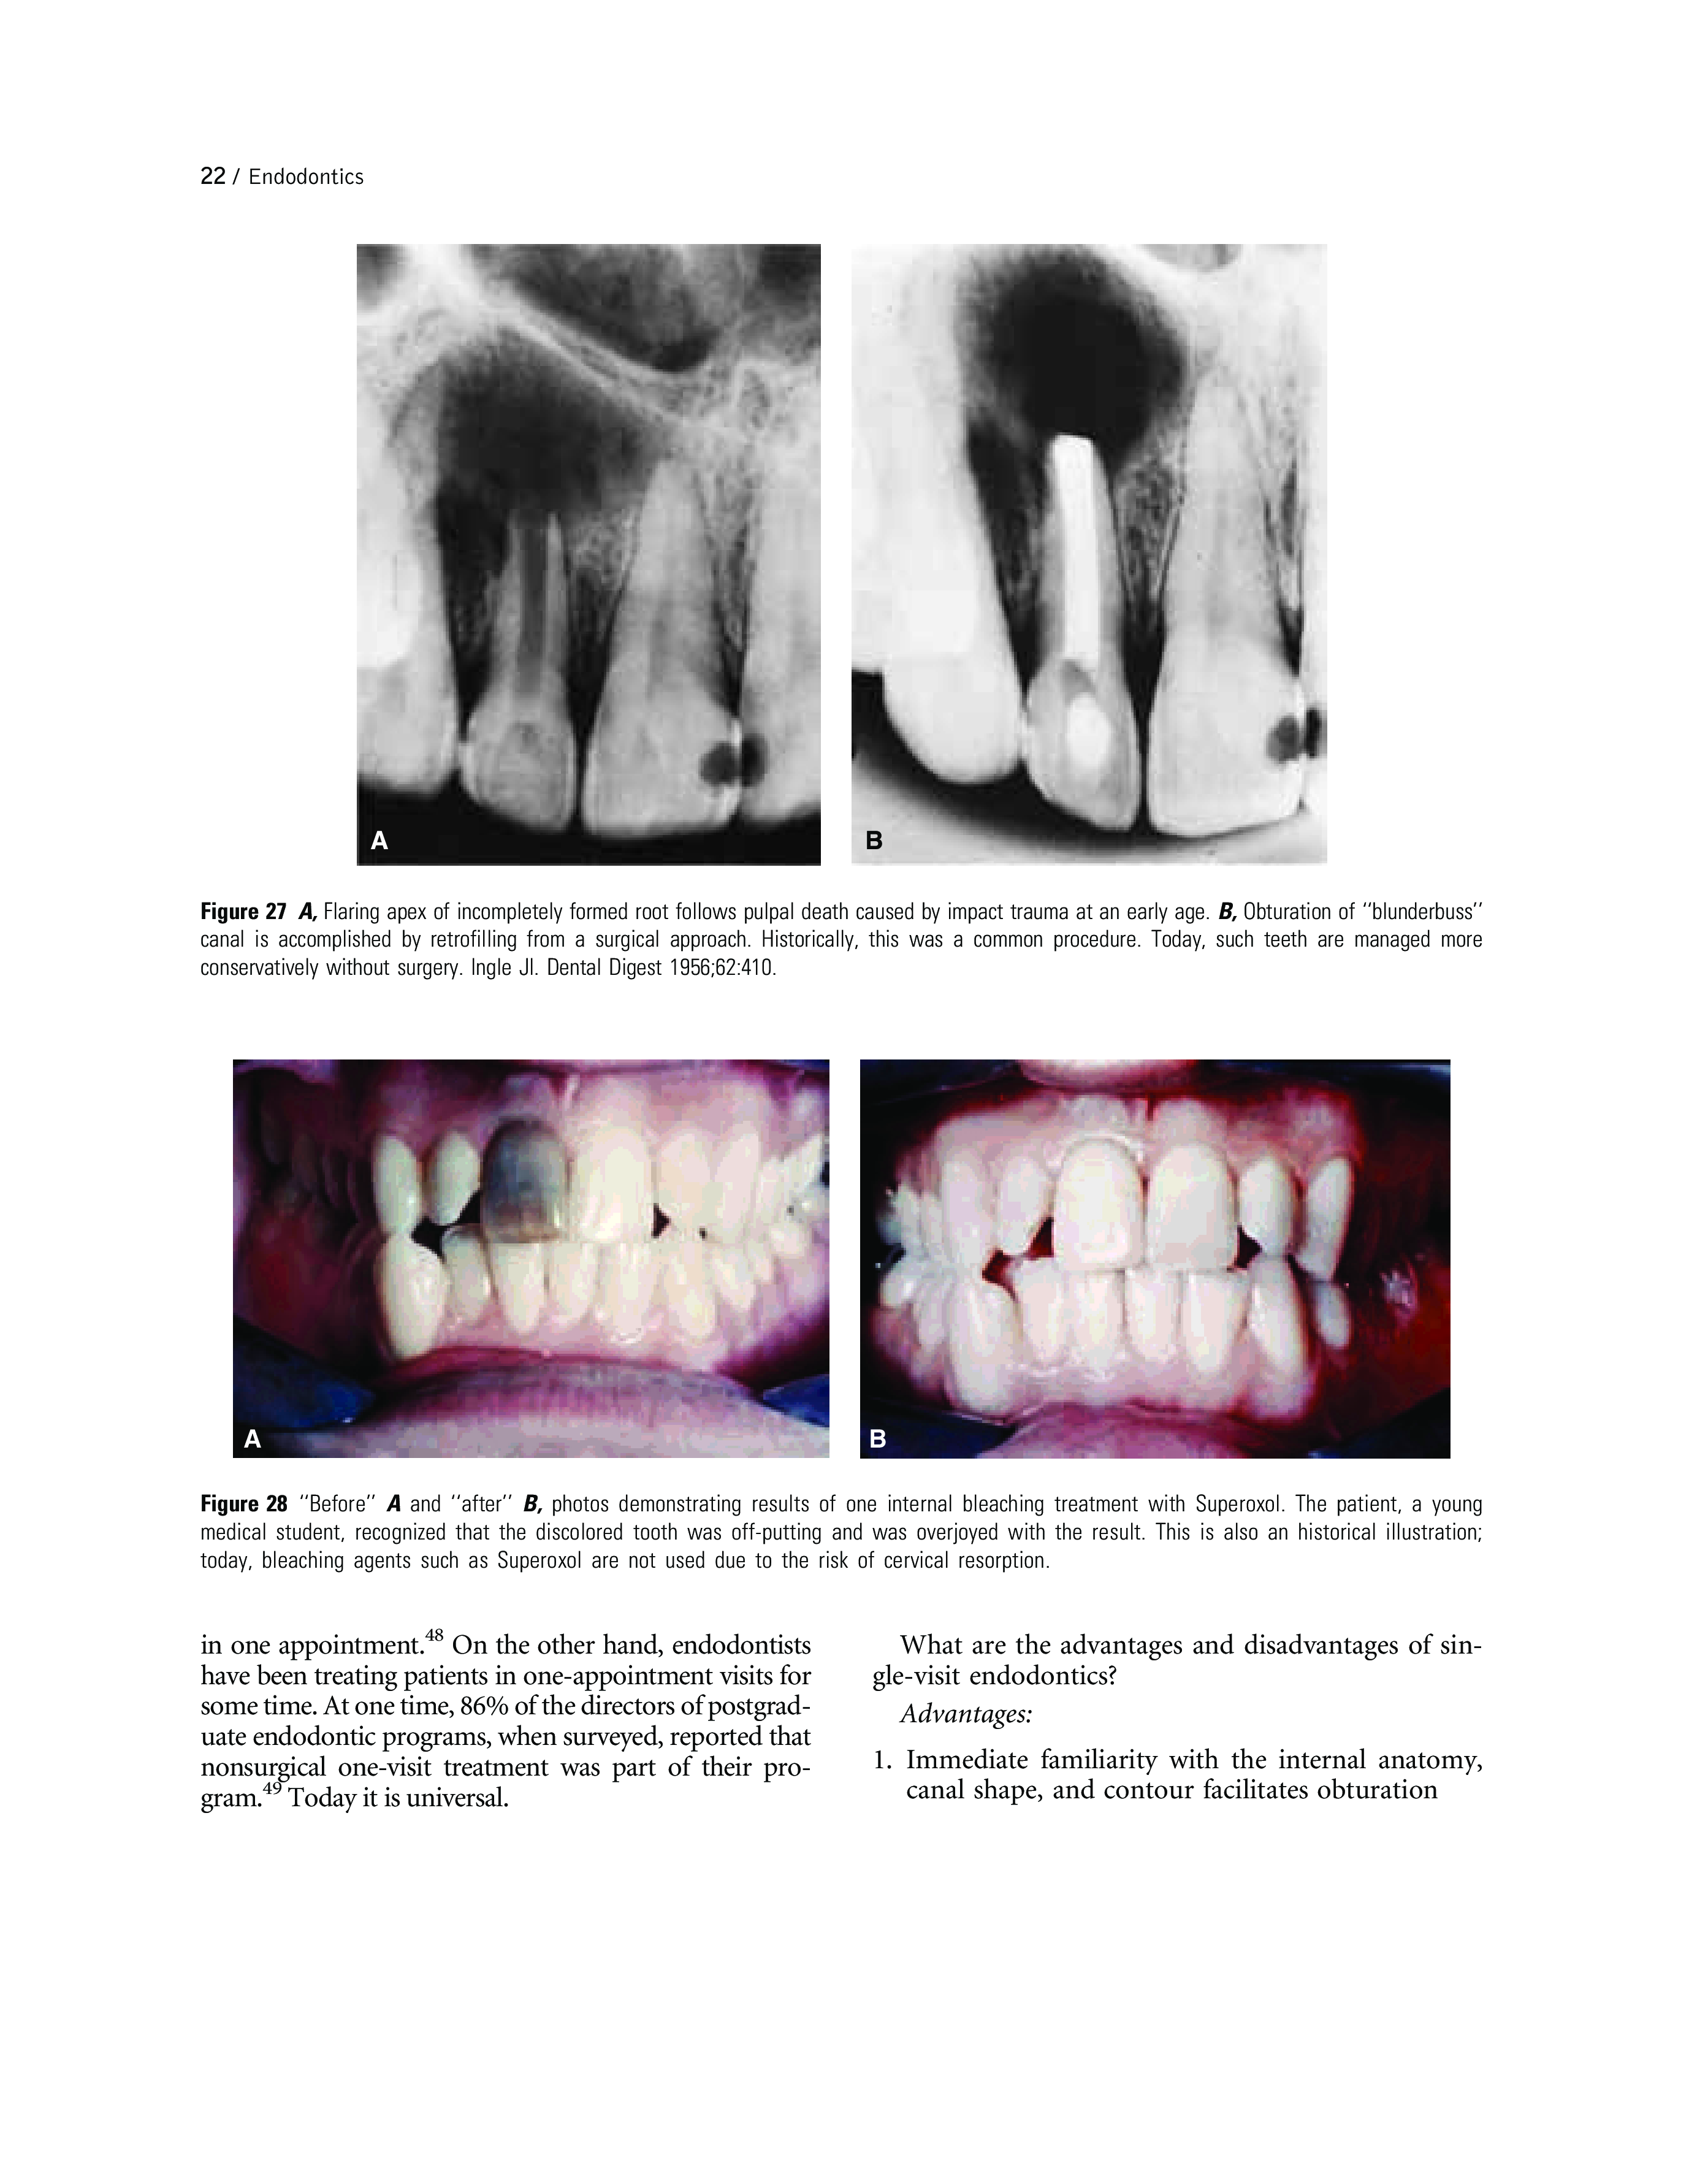

"Endodontics" - читать интересную книгу автора (John I. Ingle, Leif K. Bakland, J. Craig Baumgartner)